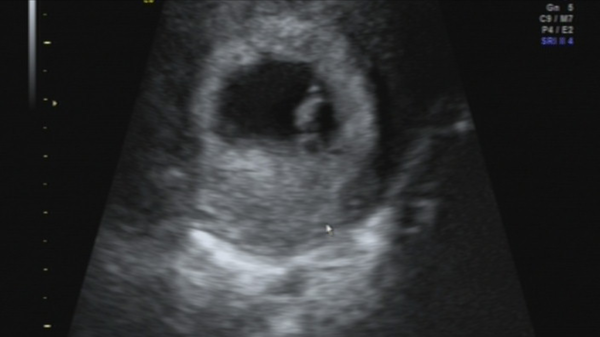

Here's my scan pic as promised! Not lots to see at 7+1, but the top big blob is the baby, and the blob under that is the yolk sac. So glad she was able to see it all via an abdominal scan rather than vag cam! I've got a retroverted uterus, which can make it harder to see, so was convinced I'd be stripping off and throwing dignity to the wind yet again... Think private clinics have much better equipment though, so blushes were spared!